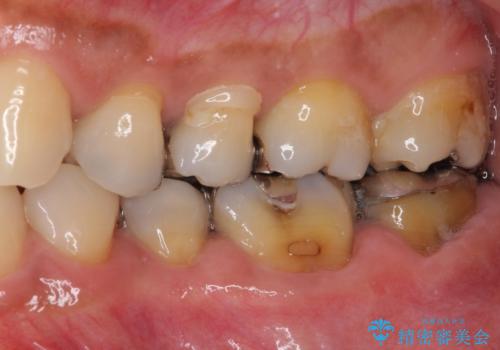

- 上下の奥歯にものが挟まりやすいことを気にして来院された患者様です。

上下ともに、やや大きいむし歯があり、そこにものが挟まりやすくなっていました。

上顎の奥歯は神経にまで虫歯が及んでいる可能性が高かったため、抜髄や断髄の可能性を考慮しながら処置を進め、セラミッククラウンにて補綴することとしました。